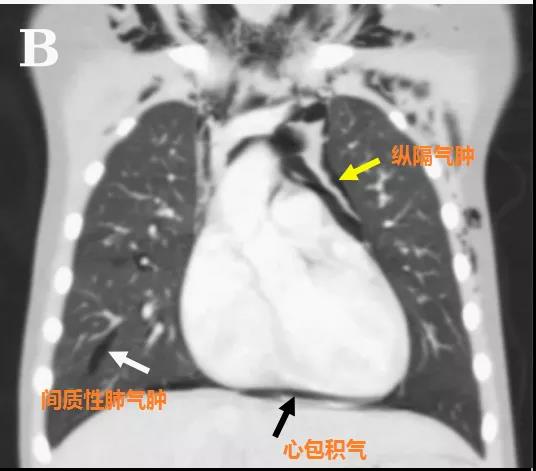

頭顱、胸部CT提示廣泛皮下氣腫、縱隔氣腫、心包積氣、甚至眼眶周圍都積氣,眼球突出!頸部無感染征象,腸管無破裂征象,看來氣體還是來自肺部。但是,肺部無感染、無肺大泡、無劇烈咳嗽,只有間質性肺氣腫。縱隔氣腫、皮下氣腫的治療,核心是根除病因,切開引流效果不像氣胸那么理想,而且縱隔切開引流還存在手術風險。找不到病因,如何是好?考慮患者是過敏體質,有皮疹,繼續(xù)呼吸機輔助呼吸,先治療過敏,肌肉注射腎上腺素、靜脈注射類固醇激素和抗組胺藥、吸入支氣管擴張劑等。經上述治療,臨床表現(xiàn)和影像學方面都有迅速的改善。隨后拔出氣管導管,口服類固醇激素出院,門診隨訪。